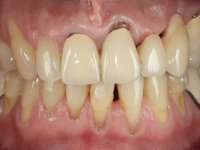

66-year-old male patient, non-smoker. It featured a 5-member metal-ceramic bridge with extreme mobility. Teeth 11 and 21 had infiltrated cervical margins. Both arches showed root exposure with signs of cervical abrasion. Composite resin “slots” were visible on the buccal surfaces of some mandibular teeth compatible with an orthodontic treatment with aligners that the patient was undergoing. After the imaging examination, it was found that the bridge's distal support, tooth 24, was irretrievably lost. The mesial pillars 11 and 21 had endodontic treatment and intraradicular posts. Teeth 25 and 26 also had endodontic treatment and extensive restorations in composite resin. In the lower jaw, two bridges were visible. In the third quadrant a 4-element bridge supported on tooth 35 and on 2 implants placed in the location of teeth 36 and 37. In the fourth quadrant a 3-element bridge supported on tooth 45 and an implant placed in the location of tooth 46. The patient presented a thick gingival phenotype and very good oral hygiene.

The patient was proposed to undergo a fixed oral rehabilitation consisting of a 2-element bridge over teeth 11 and 21 and a 5-element bridge over 3 implants that would be placed in the location of teeth 22, 24 and 26. The prosthetic structures would have an infrastructure in Zr coated with ceramic and the bridge over the implants would be screwed. The indicated extraction of teeth 25 and 26 and placement of an implant in the 26 site would imply surgery to fill the maxillary sinus. As the patient showed interest in having fixed temporary rehabilitation during treatment, we divided the treatment into 6 phases to achieve this goal: 1- Placement of a temporary bridge over teeth 11,21,25 and 26. With tooth extraction 24. 2- Placement of 2 implants in the location of teeth 22 and 24. 3- Placement of a temporary 6-element bridge over teeth 11 and 21 and over the implants. 4- Carrying out surgery to fill the maxillary sinus. 5 – Placement of the implant in the location of tooth 26 and in the area where the filling of the maxillary sinus was made. 6 – Placement of the definitive work.